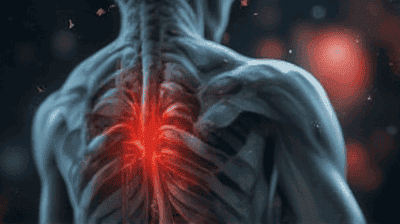

Chronic pain is a complex and multifaceted condition that affects millions of people worldwide. Unlike acute pain, which serves as a warning signal of injury and typically resolves once the underlying issue is treated, chronic pain persists long after the initial cause has been addressed—or even in the absence of any identifiable physical damage. This phenomenon can be puzzling for patients and healthcare providers alike, leading to significant physical, emotional, and social consequences. Understanding chronic pain syndromes and the reasons some individuals experience pain without physical injury is essential for developing effective treatment strategies and improving quality of life for those affected.

Chronic pain is defined as pain that persists for longer than three months or beyond the expected time of healing after an injury. It is often classified into two categories:

Primary Chronic Pain: This type of pain is not caused by an underlying medical condition but arises from changes in the nervous system and how the brain perceives pain signals. Conditions like fibromyalgia and chronic fatigue syndrome fall into this category.

Secondary Chronic Pain: This pain results from an identifiable condition, such as arthritis, cancer, or nerve damage, but persists even after the initial problem has been treated.

Physical Limitations: Pain can lead to reduced mobility, making daily activities such as walking, exercising, or performing household chores challenging.